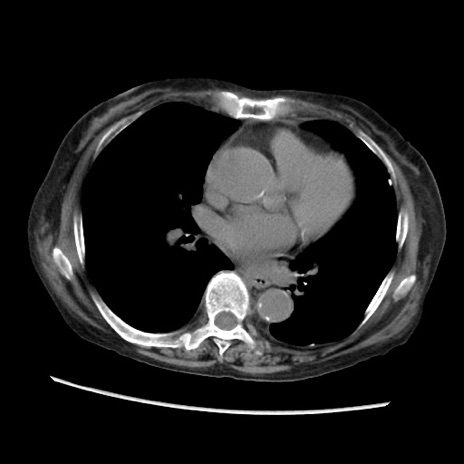

冠状断像

【症例】80歳代 女性

【主訴】腹部膨満感

【現病歴】他院にて肝硬変にてフォロー中。1週間前から便秘、腹部膨満感、臍部腫瘤あり受診となる。

【既往歴】肝硬変

【身体所見】腹部膨隆あり、皮膚変化なし、疼痛なし。

【データ】WBC 4600、CRP 0.25